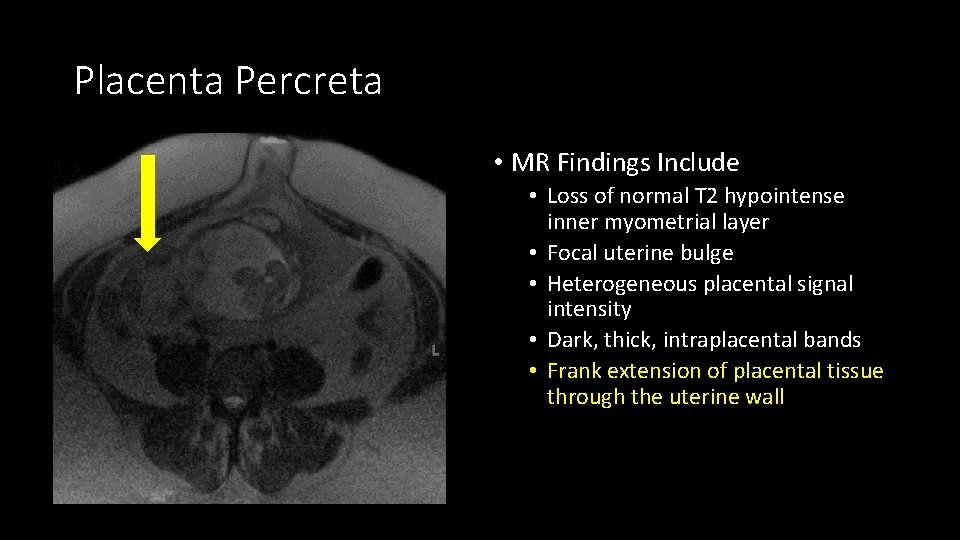

Don’t forget the placenta: Placenta Accreta • Term describing abnormal placentation wherein chorionic villi invade myometrium. • Accreta: Villi attached to myometrium but no muscular invasion. • Increta: Villi partially invade myometrium. • Percreta: Villi invade up to or beyond uterine serosa.

Placenta Accreta • MR Findings Include • Loss of normal T 2 hypointense inner myometrial layer • Focal uterine bulge • Heterogeneous placental signal intensity • Dark, thick, intraplacental bands • Frank extension of placental tissue through the uterine wall

Placenta Accreta • MR Findings Include • Loss of normal T 2 hypointense inner myometrial layer • Focal uterine bulge • Heterogeneous placental signal intensity • Dark, thick, intraplacental bands • Frank extension of placental tissue through the uterine wall

Placenta Percreta • MR Findings Include • Loss of normal T 2 hypointense inner myometrial layer • Focal uterine bulge • Heterogeneous placental signal intensity • Dark, thick, intraplacental bands • Frank extension of placental tissue through the uterine wall